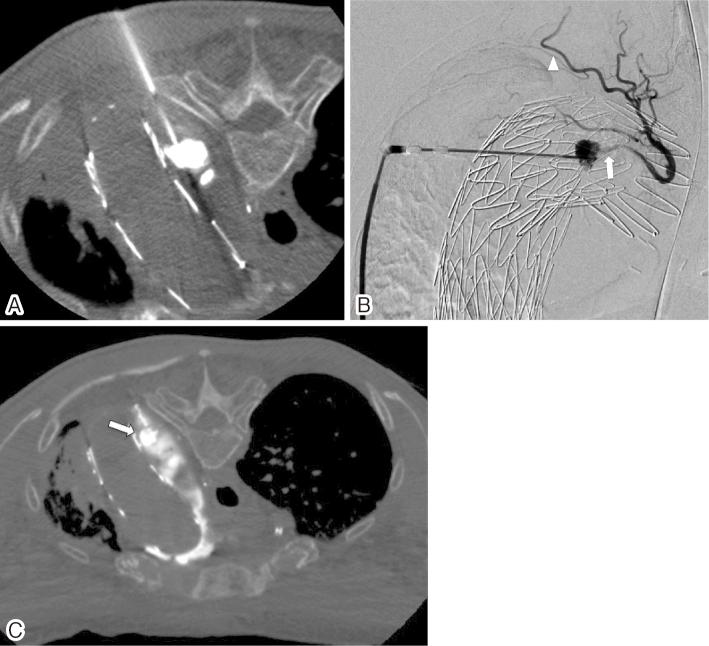

An 81-year-old woman presented with massive hemoptysis. She had a history of total arch replacement with an elephant trunk followed by concomitant antegrade thoracic endovascular aortic repair for the aortic arch and the descending aortic aneurysm. Computed tomography (CT) showed expansion of the aortic aneurysm with type II endoleak, lung parenchymal consolidation, and ground-glass opacity. An aortopulmonary fistula was suspected. Surgery posed a very high risk for the patient; hence, a less invasive approach was considered. Left subclavian arteriography revealed a type II endoleak. A transarterial approach would be difficult due to the small and tortuous access route and longer procedure time. Therefore, CT-guided puncture embolization was performed. She had no recurrence of hemoptysis for 1.4 years after the embolization.

一名81岁女性出现大量咯血。她有全弓置换并植入象鼻支架的病史,随后因主动脉弓和降主动脉瘤接受了同期顺行性胸段血管腔内主动脉修复术。计算机断层扫描(CT)显示主动脉瘤扩张伴II型内漏、肺实质实变和磨玻璃影。怀疑存在主动脉肺瘘。手术对该患者风险极高;因此,考虑采用侵入性较小的方法。左锁骨下动脉造影显示II型内漏。由于入路小且迂曲,手术时间长,经动脉途径困难。因此,进行了CT引导下穿刺栓塞术。栓塞术后1.4年,她未再出现咯血复发。